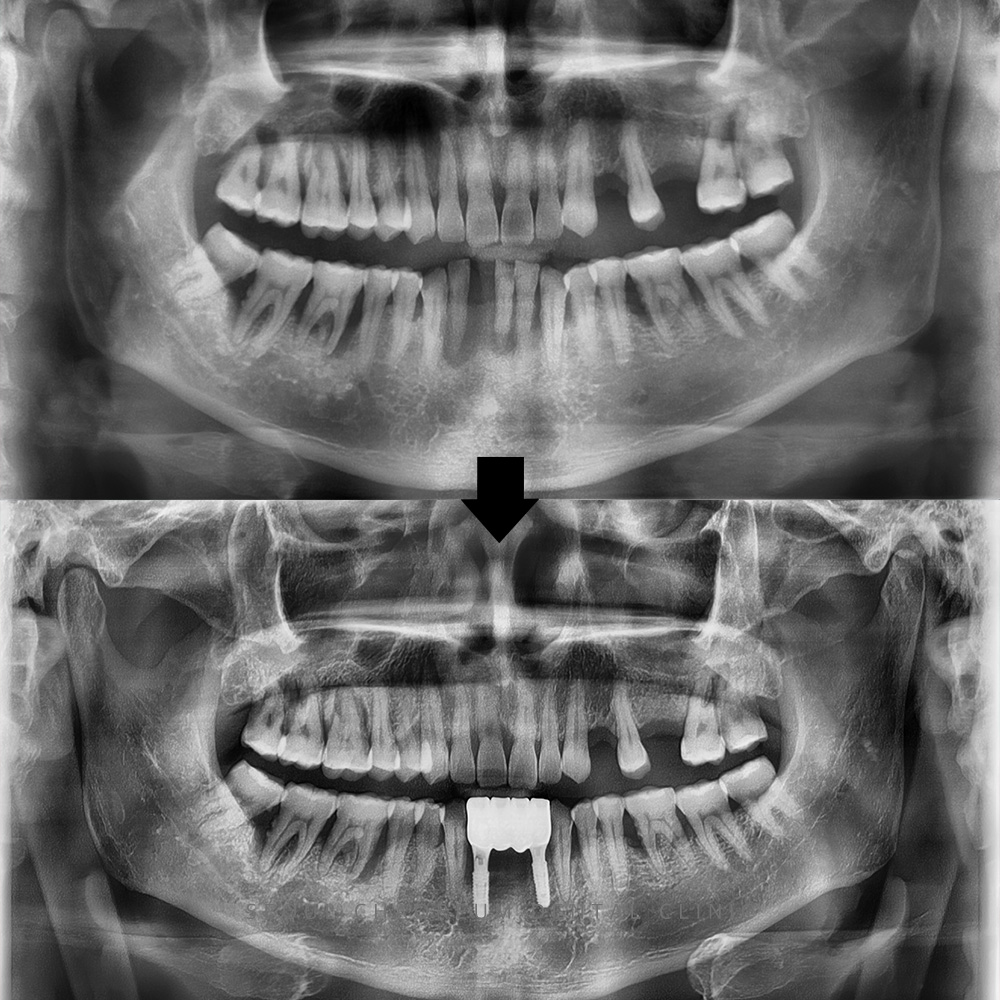

병점치과 아래 앞니 브릿지 치료가 가능한가요? 치아는 단순히 음식을 씹는 도구를 넘어, 발음과 얼굴 인상, 저작 균형까지 영향을 주는 중요한 구조물입니다. 특히 아래 앞니는 겉으로 잘 드러나는 부위인…